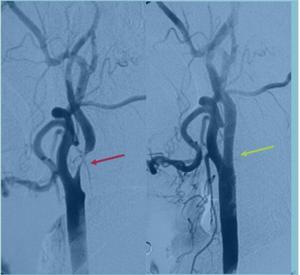

2.出血性腦血管病:腦動脈瘤(圖4),腦動靜脈畸形、動靜脈瘺、脊髓-脊柱血管畸形等。

神經介入技術(圖4 腦動脈瘤介入治療)